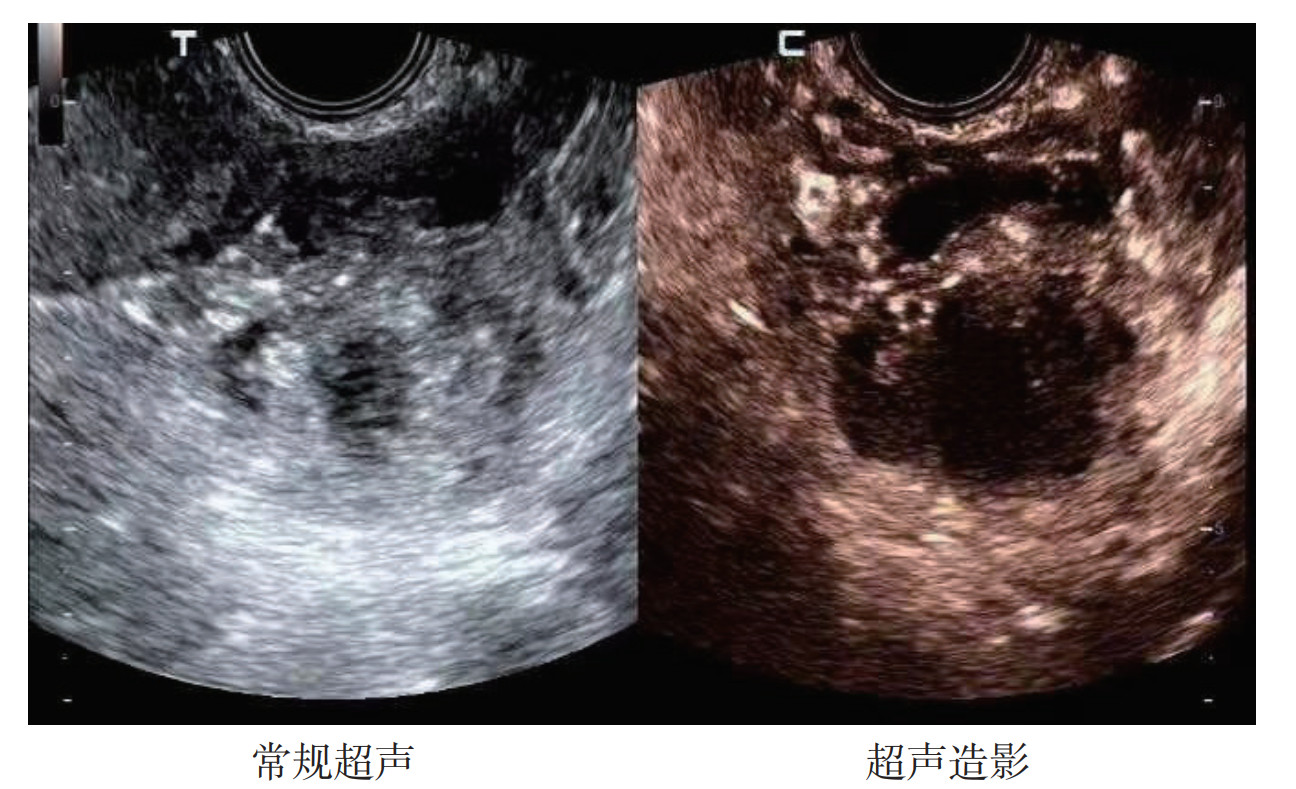

卵巢恶性肿物超声造影多呈快速早期高增强,消退时间早,增强强度高于子宫肌层灌注强度;良性肿物多呈无增强或周边环状增强。TIC曲线显示,卵巢恶性肿物始增时间和达峰时间均低于良性肿物,而恶性肿物峰值强度高于良性肿物,差异均具有统计学意义(均P<0.01,表 2,图 1)。

| 注 囊实混合性肿块,边界不清,以实性成分为主,超声O-RADS分类为4类;超声造影示,肿块实性部分早期不均匀性高增强 图 1 1例卵巢透明细胞癌的常规超声及超声造影表现 Fig.1 Routine ultrasound and contrast-enhanced ultrasound results of an ovarian clear cell carcinoma patient |